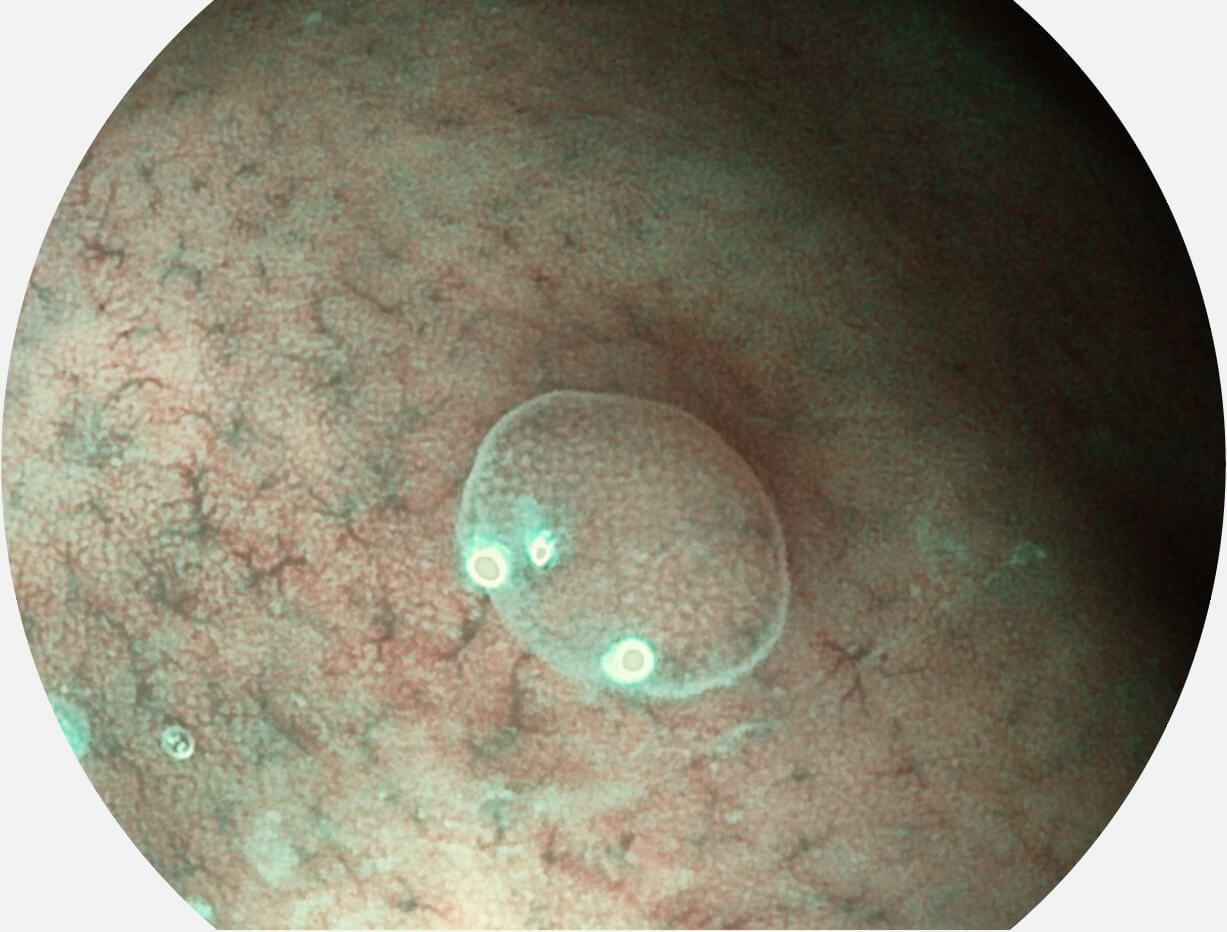

白光图像

白光图像

VIST图像

VIST图像

白光图像

白光图像

VIST图像

VIST图像

白光图像

白光图像

VIST图像

VIST图像